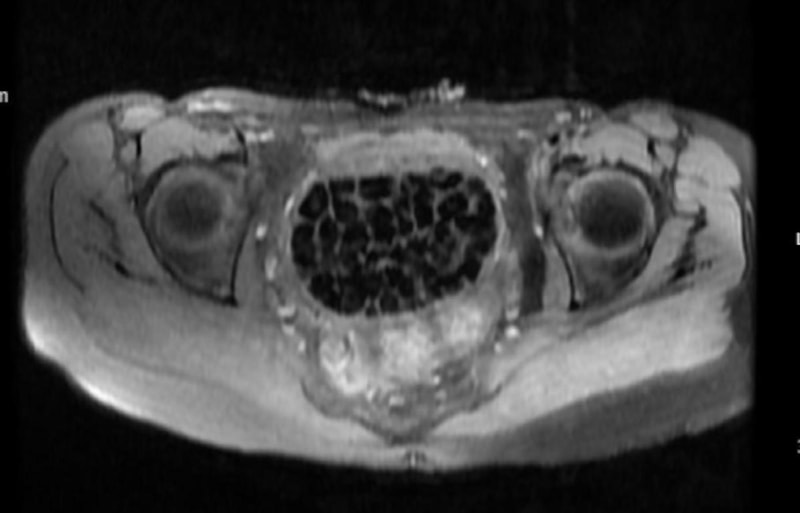

Hastasının durumuna yönelik konuşan Üroloji Uzmanı Doç. Dr. Erkan Erkan, "Hastamızın 2004 yılında doğduğunu ardından doğar doğmaz ekstrofi vezika dediğimiz 50 binde bir görülen bir anomaliden dolayı art arda ameliyatlar geçirdiğini öğrendik. 10 yaşında yine bir ameliyat geçirmişti, gerekli görüntüleme ve tetkiklerimizi yaptırdık. Normalde mesanesinin olması gereken yerin hemen arka kısmında taşlarla dolu bir kese olduğunu gördük, bunun üzerine ek görüntülemeler; MR çektirdik. Hastamız çelişkili açıklamalar almıştı, kendi radyolojik kliniğimiz ve edindiğimiz konsültasyonlarda taşların mesanede değil vajinal boşlukta oluştuğunu düşündük, bir planlama yaptık.

Kadın doğum hocamızın da çabasıyla taşları tamamen temizledik ardından ileride normal bir hayat sürmesi bakımından oraya plastik cerrahi yaptık. 287 adet taş çıkardık, pratikte gerçekten görünce çok şaşırdık çünkü bu aynı zamanda literatürde çok nadir görülen bir olay. Biz ameliyata hazırlanırken de teorik olarak biraz araştırdık. Literatürde gördüğümüz kadarıyla buna benzer bu tanıma uyan bir vaka vardı. Literatürde sanırım yayınlanmış 2’nci vaka olacak. Farkındalık çok önemli, bilinçli bir hastamız vardı. Doğumsal anomaliyle doğan çocuklarımızda ileride bunlara bağlı bazı sıkıntılar çıkabileceğinin öngörülmesi lazım. İlgili tedavilerini alsalar bile düzenli takiplere gelmeleri gerekiyor. İleride eğer dikkat etmezse ki zannetmiyorum, tekrarlayabilir. Bu rahatsızlık ekstrofi vezikal epispadias durumu, çok nadir bir durum." dedi.

Genç kızın uzun süredir devam eden karın ağrısı olduğunu söyleyerek sözlerine başlayan Jinekolojik Onkoloji Uzmanı Op. Dr. Emin Erhan Dönmez, "Mesane taşları olduğu düşünülerek daha büyük bir hastaneye refere edilmiş. Aramızda mini bir konsey yaparak muayene ettik. Vajen bir hazne görevi görerek orada durağan bir idrar, uzun süre beklediği için idrar içindeki minerallerde çökerek taşlar oluşmuş. Mesanedeki idrarın vajene akmış olabileceği ve vajende göllenen idrar nedeniyle taşların burada oluşacağını düşündük, ameliyatımızı planladık. Ameliyata tanı amaçlı girmiştik, sistoskopi (Mesane gibi idrar yollarını kapsayan kısımlardaki rahatsızlıkların teşhis ve tedavisinde kullanılan endoskopik bir yöntem) dediğimiz ameliyatı Erkan Hocam ile birlikte gerçekleştirdik.

Önce mesaneyi bir görüntüledik, mesane tabanına yaklaşık 2-3 cm’lik bir alandan vajene fistülize olduğunu gördük. Mesaneden vajene geçtiğimiz esnada tüm vajenin taşlarla dolu olduğunu gördük. Tanı amacıyla girdiğimiz ameliyatta her şey de olağan gittiği için tedaviye geçtik. Taşların çıkabileceği kadar bir genişlik sağladık. Daha sonra yaklaşık en büyüğü 2,5 cm boyutlarında olan, irili ufaklı 287 tane taşı ameliyat esnasında çıkarmış olduk. Taşların tekrarlamaması için idrarın göllenmemesi, en azından dışarıya rahatça boşalabilmesi için vajinal rekonstrüksiyonu sağladık. Ameliyatta da herhangi bir problem yaşamadık. Literatürü Erkan Hocam ile birlikte değerlendirmiştik. Primer olarak vajende birikmiş olan bu kadar çok sayıda taşla ilgili bir makale görmedik, rastlamadık." dedi.